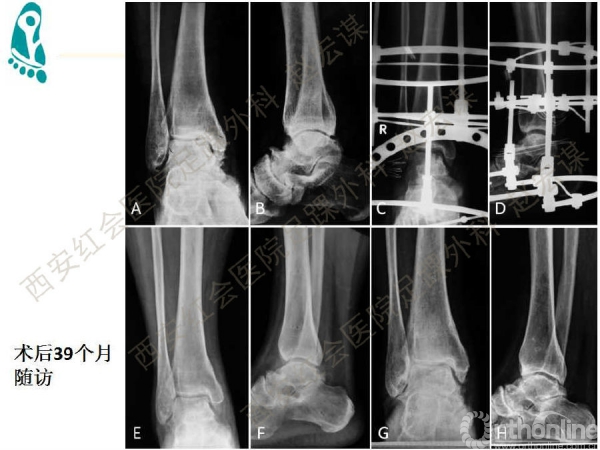

踝关节骨关节炎的发生率呈整体上升趋势,关节融合与置换作为终末期的治疗标准,均存在一定缺陷。而早起保守治疗与保关节手术治疗逐渐得到临床重视,但治疗指证与治疗方法的选择比较困难。该课件内容系统阐述了目前踝关节骨关节炎的保守治疗选择进展,对临床合理开展保关节治疗有较高的参考价值。